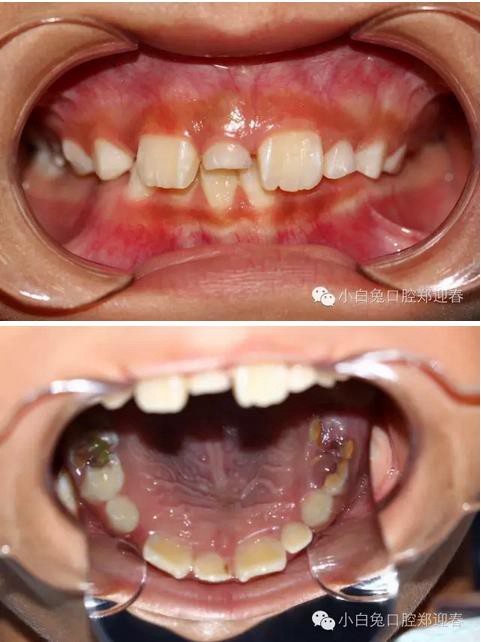

患兒,男,8歲半,混合牙列,11、12均已萌出,其間有一重度磨耗的51滯留,家長一直不知怎么回事,因為美觀問題,至當(dāng)?shù)卦\所給予檢查,也許條件受限沒有X光牙片機(jī)的緣故,建議直接拔除51,然后矯正關(guān)閉間隙,家長不放心,來診,常規(guī)拍攝X線片發(fā)現(xiàn)乳牙滯留和間隙存在的原因是有一埋伏倒置多生牙的緣故,遂建議拔除滯留的51和埋伏的多生牙,然后擇期矯正。

360截圖20170120144343560.jpg

X線片:51牙根基本吸收,下方顯示倒置多生牙。